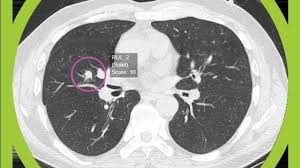

The Symptoms Of Lung Cancer In Males And Females from www.candrol.com Inflammation or infection of the lung (pneumonia) Symptoms of lung cancer develop as the condition progresses. Find out more about these and other symptoms. While a cough that doesn't go away or gets worse is. There are sometimes no signs or symptoms in the early stages of lung cancer, and sometimes these small cancers are found on scans when people are being treated for different things. See a gp if you have symptoms of lung cancer, such as breathlessness or a persistent cough. Rarer types of cancer, such as soft tissue sarcomas, can also develop in the lungs. Autoimmune conditions, such as rheumatoid arthritis and lupus, are other possible causes of pleurisy.

The main symptoms of lung cancer are listed below. Because the cancer is at the top of the lungs, it might put pressure on or damage a group of nerves that runs from the upper chest into your neck and arms. While a cough that doesn't go away or gets worse is. A new cough that doesn't go away; Some of the most common are horner's syndrome, superior vena cava syndrome, and paraneoplastic syndrome. The main symptoms of lung cancer include: You don't need to try and remember all the signs and symptoms of cancer, but we have listed some key ones to give you an idea of the kind of things to be aware of. Cancer cachexia, a syndrome including unintentional weight loss and muscle wasting, is very common in the later stages of cancer. They can advise about nicotine replacement therapies and prescription medicines that can greatly increase your chances of quitting successfully. Around 47,000 people are diagnosed with the condition every year in the uk. There are sometimes no signs or symptoms in the early stages of lung cancer, and sometimes these small cancers are found on scans when people are being treated for different things. The symptoms of a secondary lung cancer may be distressing, and can include: Later, it often causes coughing, wheezing, and chest pain.